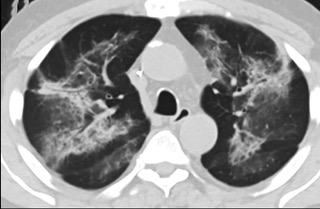

疑點一,電子煙患者的CT影像和臨床表現并不具有特異性。所謂美國電子肺炎患者,其實是對沒有其他合理診斷證據、吸食電子煙肺炎患者的統稱。這些患者在病發前90天內吸食了電子煙,尤其值得注意的是,部分患者的CT影像特征和臨床表現與病毒性肺炎患者極其相似。

中、下肺軸位CT平掃顯示毛玻璃樣混濁伴胸膜下保留。(同一病人CT影像)

中、下肺軸位CT平掃顯示毛玻璃樣混濁伴胸膜下保留(箭頭)。(同一病人CT影像)